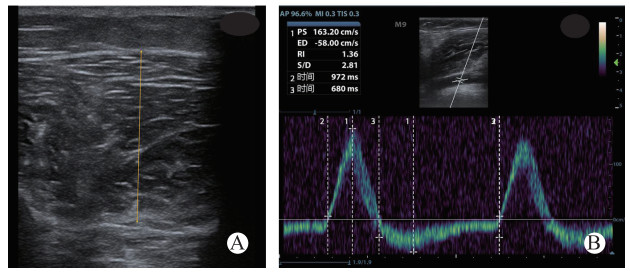

1.1 研究对象准备及模型建立研究开始前收集志愿者的一般信息,包括姓名、性别、年龄、身高、体质量,计算BMI。取双侧小腿围最大处水平用软尺测量腿围,并做标记。便携式超声机(M9,深圳迈瑞生物医疗电子股份有限公司,中国)测量双侧小腿胫前筋膜室厚度,使超声探头垂直于皮肤、测量胫前筋膜室内皮下组织与筋膜室交界处到胫腓骨间膜的距离[18],见图 1A。

| PS:收缩期最大血流速,ED:舒张期最小血流速,RI:阻力指数,时间2为一个心动周期总时间,时间3为舒张期反向血流时间。 图 1 小腿胫前筋膜室厚度(A)和下肢动脉多普勒血流频谱测量(B) Fig 1 A: Measurement of the limb anterior compartment thickness; B: Measurement of Doppler blood flow waveform of limb arteries. |

采用前述超声机,使用线阵探头(L12-5Q)监测外周血管血流多普勒频谱,测量腘动脉(popliteal artery, PA)的直径(PA diameter, PAD)、横截面积(PA area, PAA)、收缩期最大血流速(PA systolic velocity, PAVs)、舒张期最小血流速(PA diastolic velocity, PAVd)、阻力指数(PA resistance index, PARI)及舒张期动脉反向血流比(PA diastolic retrograde artery flow ratio, PADRAFR); 腘静脉(popliteal vein, PV)的直径(PVD)、横截面积(PVA)、收缩期最大血流速(PVVs); 足背动脉(dorsal artery, DA)的收缩期最大血流速(DAVs)、舒张期最小血流速(DAVd)、阻力指数(DARI)、正向动脉血流比(DA systolic forward artery flow ratio, DASFAFR)及parvus tardus波形比(DA parvus tardus waveform ratio, DAPTWR)。PADRAFR为腘动脉一个心动周期内舒张期反向血流时间与心动周期时长比值; DASFAFR为足背动脉一个心动周期内正向血流时间与心动周期时长比值; DAPTWR为足背动脉前向主血流内舒张期血流时间与收缩期血流时间比值。超声检测部位及探测血管的角度保持一致,声束方向与血流方向夹角小于60°。频谱测量至少连续3个周期,取3个周期测量值的平均值为测量结果(见图 1B)。